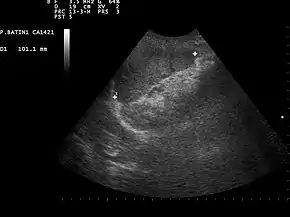

Ultrasound image of a normal spleen that may be seen in part of the eFAST

2. Left Upper Quadrant of the abdomen (Perisplenic view). Left upper quadrant is examined by working your probe down the midaxillary line starting at the left 8th rib to the 11th rib. This examines for free fluid around the kidney and spleen.